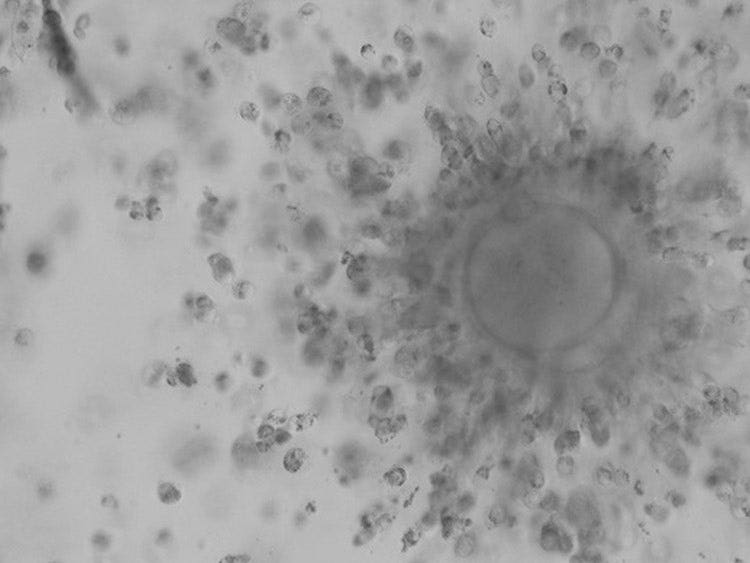

• 奥林巴斯的浮雕相衬可以在不受塑料培养皿偏光效应影响的情况下对卵母细胞进行3D成像,让您能够检查透明带的状况。

• 甚至在卵丘细胞被剥离之前,就可确认颗粒细胞在透明带上的粘附状态。